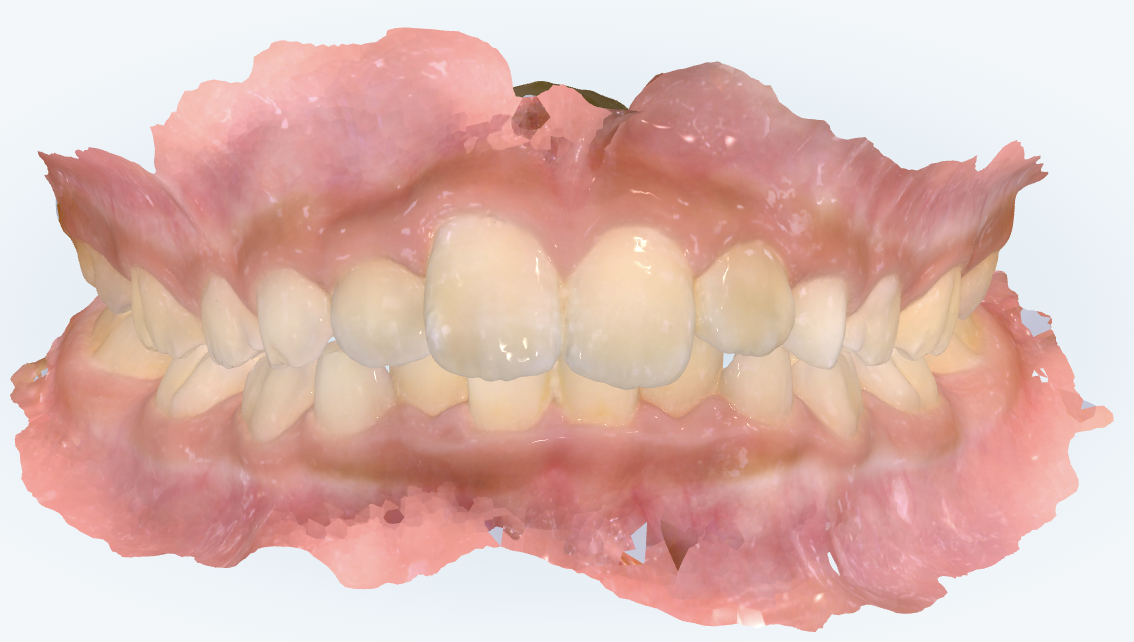

初診時の画像診断

上下の歯並びにガタガタがあります。

前歯の関係が出っ歯になっています。

前から見ると、上の前歯が下の前歯より少し前に出ていて、“軽い出っ歯傾向”があります。ただし、出っ歯の程度は軽度のレベルです。

はい。今回のケースでは、上の歯並びよりも下の歯並びに大きいガタガタがある結果、下が内側に入り込むことで、上が相対的に前に出て見えるという理由で、軽い出っ歯傾向が出ていると考えています。